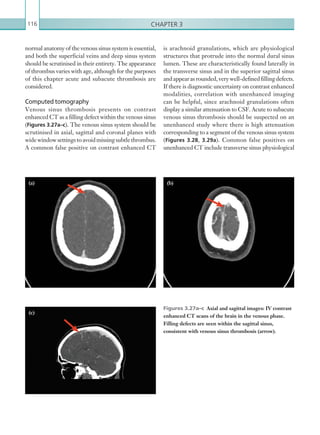

Two-level PE Wells score

PE likely (4 points)

Is CTPA* suitable** and available immediately?

Yes No

Offer CTPA